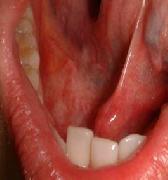

舌根部がん(舌後方のがん)